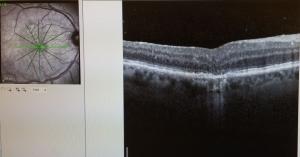

Τι είναι η απόφραξη φλέβας του αμφιβληστροειδούς.

Η απόφραξη φλέβας του αμφιβληστροειδούς είναι μια πάθηση στην οποία η κεντρική ή κάποια περιφερική φλέβα σε κάποιο σημείο της είναι τόσο στενή που η ποσότητα του αίματος που περνάει από αυτήν δεν επαρκεί.